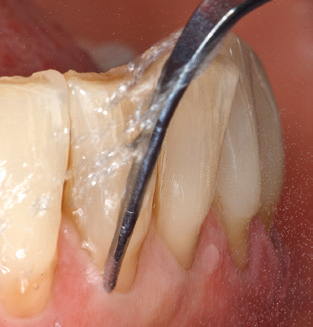

Nach der maschinellen Reinigung der Zahn und Implantatoberflächen erfolgt eine manuelle Instrumentierung der natürlichen Zahnoberflächen mit konventionellen Handinstrumenten. Bei der manuellen Reinigung ist insbesondere auf einen korrekten Anstellwinkel, eine ausreichende Schärfe, eine gute Abstützung und auf eine von apikal nach koronal gerichtete Arbeitsweise der Kürette zu achten. Zur Nachinstrumentierung der Implantatkonstruktionen sollten entweder Titan oder Carbonküretten verwendet werden (Abb. 8). Ergänzend zum Einsatz von Ultraschallgeräten können in der Erhaltungstherapie auch Pulverstrahlgeräte genutzt werden. Dabei ist jedoch zu berücksichtigen, dass diese Verfahren nicht zum Entfernen harter Beläge geeignet sind und daher die Verwendung von Hand oder Ultraschallinstrumenten nicht komplett ersetzen können. Abschließend erfolgt in jedem Fall eine mechanische Politur der zugänglichen Zahn und Implantatoberflächen mit Polierkelchen und Polierpasten (Abb. 9).